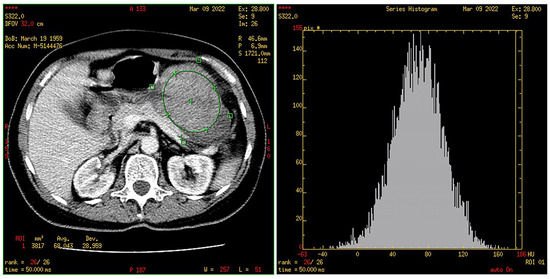

2.4. CT Texture Analysis